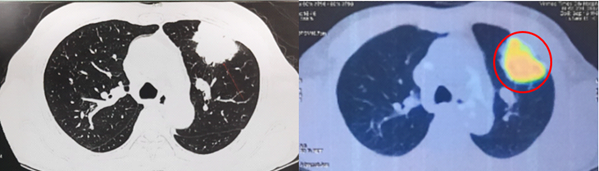

- Cắt lớp vi tính lồng ngực có tiêm thuốc cản quang:

Hình 1. Khối u kích thước 51x58x42mm thùy trên phổi trái, ngấm thuốc không đều sau tiêm (vòng tròn đỏ).

Hình 6: Hình ảnh khối tăng chuyển hóa FDG ở thùy trên phổi trái tương ứng với tổn thương nguyên phát đã biết (vòng tròn đỏ) (cT3).